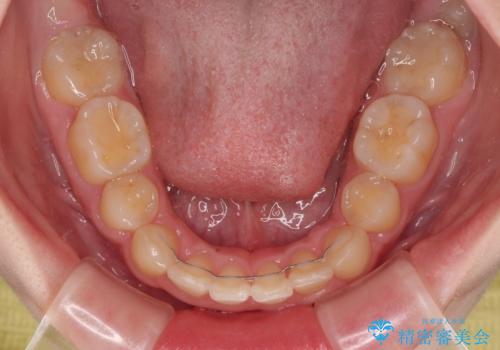

下の前歯が隠れてしまうほど深く咬みこんでいたため、上顎前歯が前方に突出しているような印象がありましたが、咬み合わせが改善され、整った口元に仕上げることができました。

- デコボコになっている前歯を気にして来院された患者様です。

口元の突出感は気になっていないものの、デコボコを解消すると口元が前方に突出する可能性があるため、上下左右の第一小臼歯4本を抜歯して、ワイヤー装置にて矯正治療を行うこととしました。